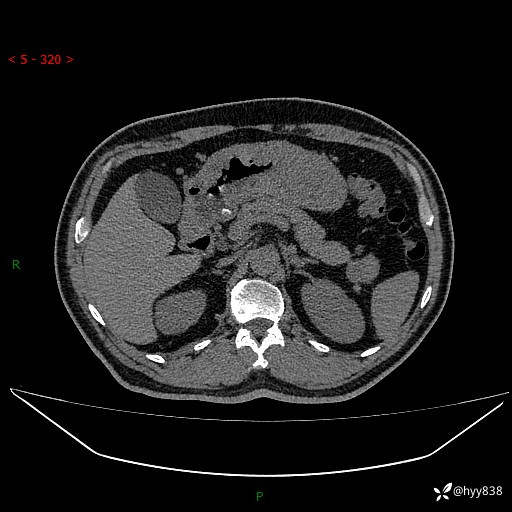

增强动脉期